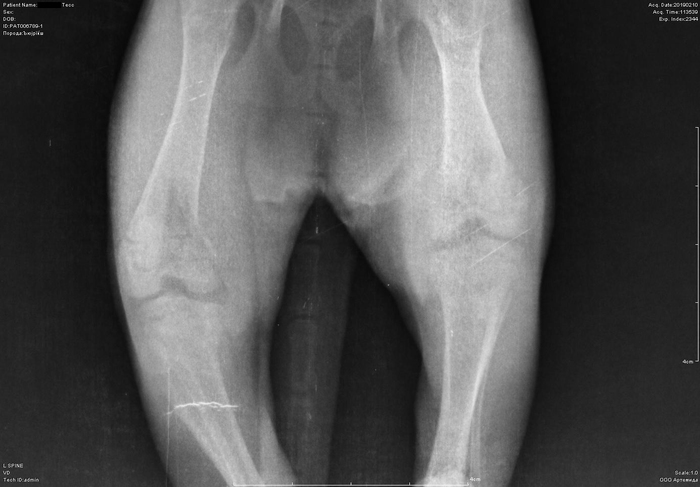

Рентген котенка

Добрый день. Котенок рожден 5 ноября 2018 года, девочка, не привита. Проглистована. Неожиданно в один момент стала припадать на задние ноги. Как бы бережет их и старается не прыгать лишний раз. Свозили два дня назад к ветеринару - всю её прощупал, говорит переломов нет, вывихов тоже. Сделали блокаду ближе в крестцу новокаина, чтобы снять симптомы. Прописал кальций в таблетках Ексел. Сейчас всё примерно так же - лапки задние бережет, но стала по активнее. Прошу специалистов, если такие тут бывают, оценить снимки, т.к. врач ещё кое-что сказал и хотелось бы услышать ваше мнение. Скан расшифровки и д/з потом приложу.